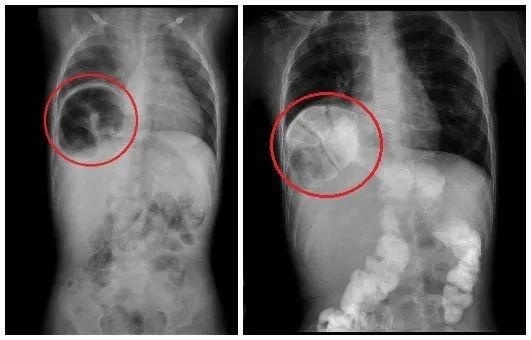

术前胸片及造影提示胃突入右侧胸腔小儿外科廖凤文主任介绍,先天性食道裂孔疝发病率低,像宇宇这么严重的更是少见,手术是目前唯一的治疗方法。食管裂孔疝传统的经胸或者经腹开刀手术,创伤大,恢复慢、并发症多、易复发。而经腹微创手术克服了这些缺点,术后胃肠功能两三天就可以恢复,且几乎看不见手术疤痕,随着腔镜技术的发展,已经成为首选的手术方式。但患儿腹腔空间小,手术部位深,毗邻心脏、肺脏、大血管和重要神经,手术难度极大,技术要求非常高。经充分讨论,该院决定挑战柳州市首例全腹腔镜下食管裂孔疝矫治手术,让患儿在最小的创伤下获得康复。宇宇的手术由经验丰富的欧阳昱副主任医师主刀,韦凯及易庆医师协助。医生在患儿腹壁上打 4 个 5 毫米的小洞,将 '' 串门 '' 的胃、结肠等重新拉回到腹腔,切除巨大的疝囊,缝合修补食管裂孔,并进行胃底折叠术,防止胃食管反流。由于宇宇是最严重类型的食管裂孔疝,手术难度大,经过几位医生的通力协助,4 个小时后,复杂的重建手术顺利完成。

专家科普食管裂孔疝是一种先天性疾病,是出生前食管裂孔未发育完整,胃大部分从腹腔突入胸腔引起的一种疾病,以呕吐和反复的肺炎为主要表现,对孩子的生长发育影响巨大。宇宇的整个胃和部分肠道,通过食管裂孔已经进入右胸腔内,占据了右侧胸腔的半壁江山。孩子近期呕吐、营养不良、体重下降、内环境紊乱都与此有关。

术后,宇宇恢复顺利。复查胸腹片提示,胃已降至正常位置。恢复进食后,宇宇没有再出现呕吐,目前已经康复出院。